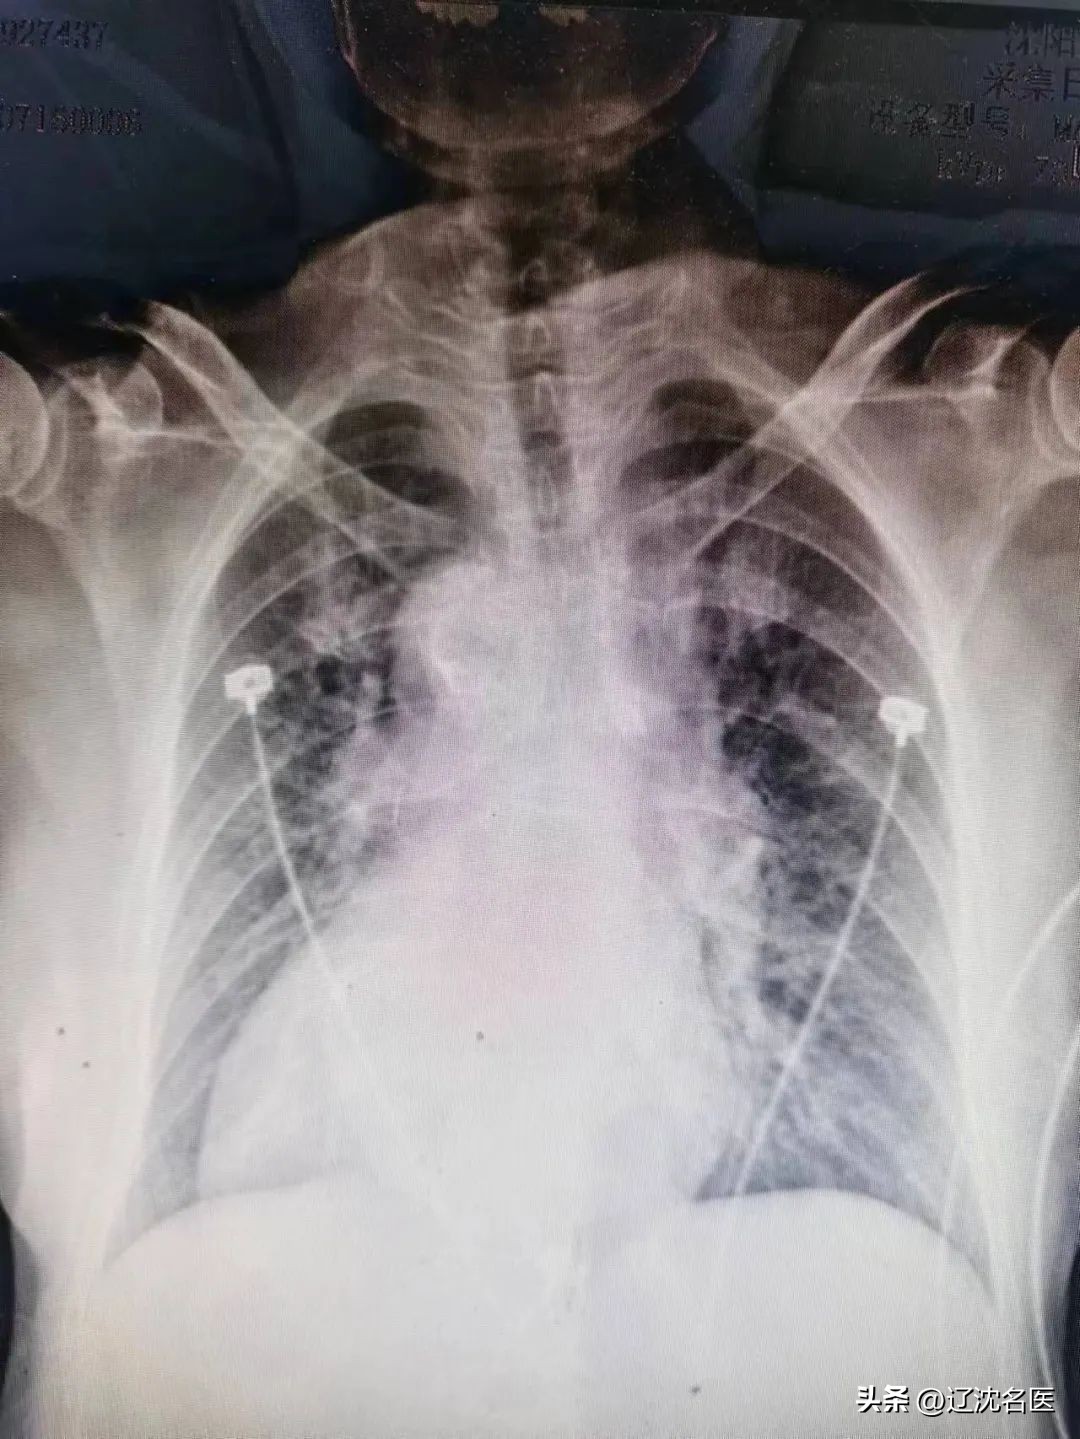

沈阳市十院急诊科,78岁的李大姨胸痛剧烈,病情危重,心电图提示胸前导联ST段弓背向上抬高0.1-0.3mv,心肌损伤标志物数以万计。心脏中心佟铁壁主任第一时间赶到急诊,初步诊断急性前壁心肌梗死。检查时发现异样,心电图导联疑似左右手接反,而且左侧胸壁听不到心音,佟主任经过详细询问病史,查体及阅图,明确诊断患者为镜面右位心,右位心在临床上本就少见,合并急性心肌梗死的情况更是非常凶险,给医生心理及技术层面带来巨大的挑战!

术前